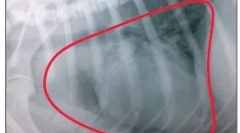

Tumori kostiju

Tumori se mogu pojaviti u različitim dijelovima skeletnog mišićnog sustava - kosti, zglobova, spojnih tkiva udova.